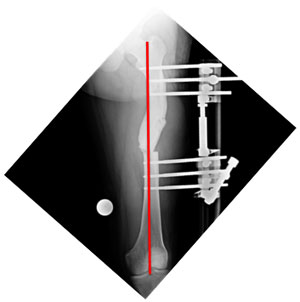

This 30 year old gentleman had met with an accident about 2 years back, following which there was a fracture of the left femur (thigh bone). He was treated at the local hospital where plating was done. The fracture healed and the plate was subsequently removed. He presented to us with deformity, shortening and awkward gait. The pictures here show the curvature in the thigh. The picture on the left shows an abnormal curvature of the thigh (red line) when we look from the front. The picture on the right shows the curvature of the thigh when we look from the side. Though it is a little proximal than normal, it is normal. |

| The x-rays at presentation showing the angulations of the femur at the fracture site. The picture on the left is as seen from the front with red lines showing the axes of the upper and lower segments. The angle between the two axes was about 34°, which should be 0° normally. The picture on the right is from the side and shows the angle between the axes (red Lines) to be about 20°, which is about 12-14° normally. |